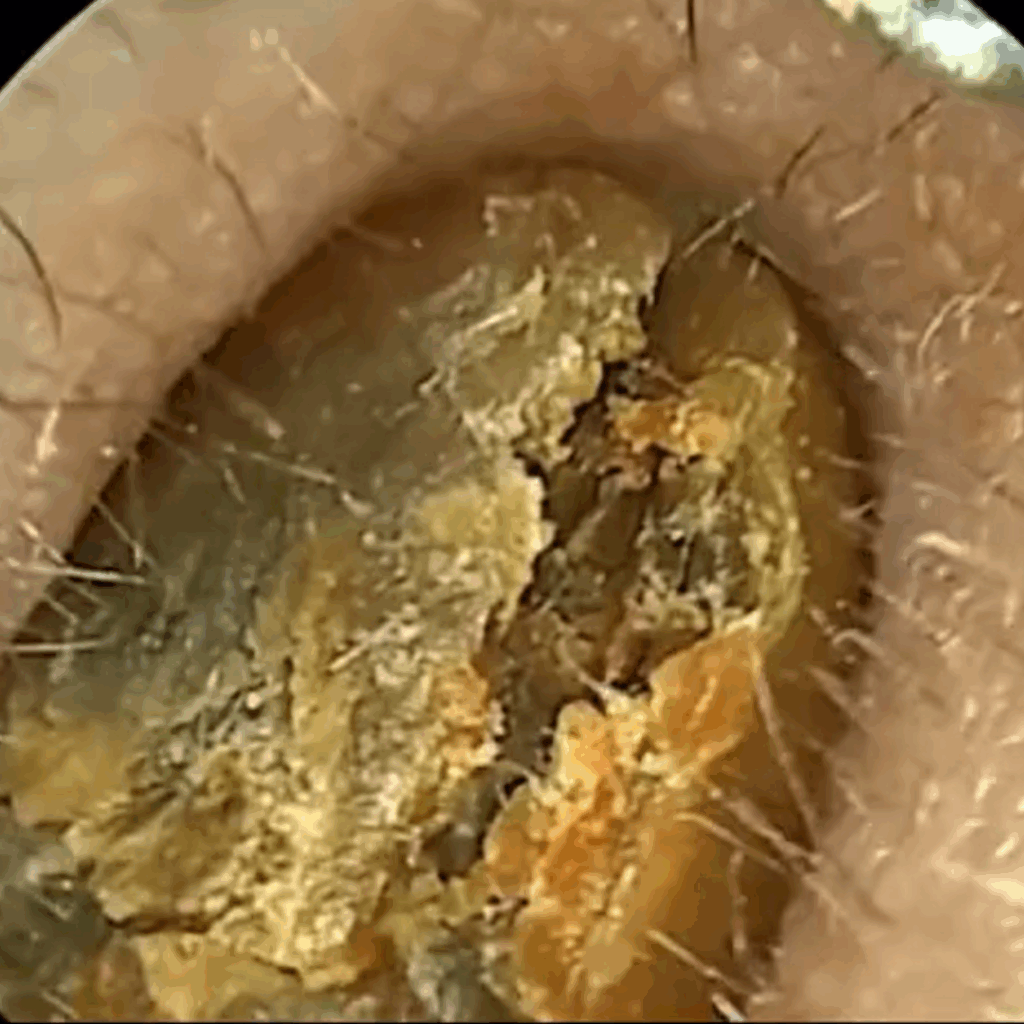

Koniec z ryzykiem urazów i infekcji — patyczki często powodują podrażnienia, infekcje i perforację błony bębenkowej. Pełna kontrola dzięki obrazowi HD 1080p — widzisz woskowinę i swobodnie ją usuwasz, zamiast ją wpychać.

Pełna kontrola dzięki obrazowi HD 1080p — widzisz woskowinę i swobodnie ją usuwasz, zamiast ją wpychać. Miękkie silikonowe końcówki zamiast patyczków — precyzyjnie usuwa woskowinę, bez ryzyka zarysowań i dyskomfortu